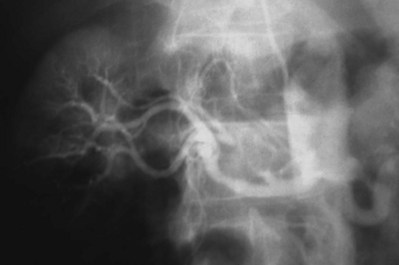

Proposed benefits of preoperative RAE include shrinkage of an arterialized tumor thrombus to ease surgical removal, reduced blood loss, facilitation of dissection due to tissue plane edema, ability to ligate the renal vein before the renal artery at time of nephrectomy, and modulation of the immune response (Klimberg et al, 1985; Bakal et al, 1993; Kalman and Varenhorst, 1999; Schwartz et al, 2007; Wotkowicz and Libertino, 2007; Wszolek et al, 2008). Ligation of the renal vein before the renal artery is useful in the setting of hilar tumors, tumors with significant medial extension, or considerable perihilar adenopathy (Schwartz et al, 2007; Wotkowicz and Libertino, 2007; Wszolek et al, 2008). Before ligating the renal vein, one should characterize the completeness of embolization to prevent unnecessary blood loss in cases of incomplete embolization. In the senior author’s experience this assessment can be made by evaluating renal venous return during surgery. In addition, angioembolization can also be useful for renal tumors associated with large arteriovenous malformations that are having a deleterious hemodynamic impact (Figs. 54-16 and 54-17).

Figure 54–16 Noncontrast (A) and contrast-enhanced (B) CT images of a patient with high output cardiac failure secondary to arteriovenous malformation associated with left renal cell carcinoma. Notice the equal contrast intensity of the aorta, left renal artery, and left renal vein.

Figure 54–17 A, Left selective renal angiogram demonstrates immediate filling of the renal vein and inferior vena cava. B, Angiogram after placement of coils demonstrates complete angioinfarction. Contrast medium in the contralateral renal pelvis confirms contralateral renal function.